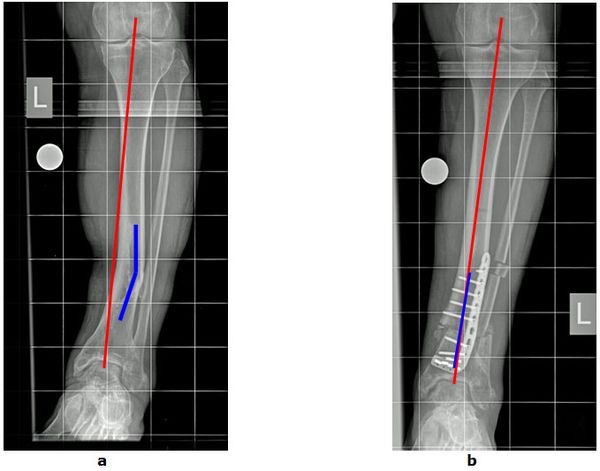

Abb.2: a O-Bein Fehlstellung durch Knick im Unterschenkel (blaue Linie) nach einem Knochenbruch. Der Patient klagt durch die Fehlbelastung über Schmerzen im Sprunggelenk. Eine Arthrose ist bereits eingetreten.

b Begradigung der Beinachse durch eine gelenknahe Knochenumstellung mit Entlastung der Arthrose.